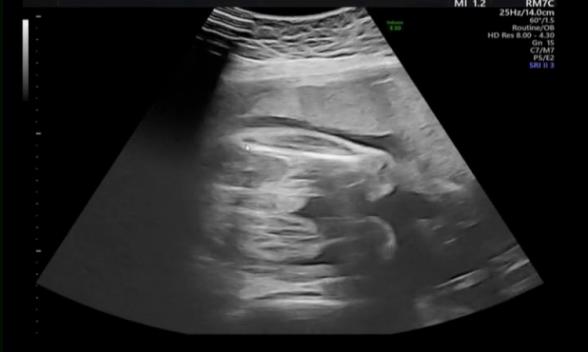

突然申し訳ないのですが、このエコーを見て、しっかり男の子の外性器はついているなと感じますでしょうか?。>_<。

性別は男の子と言われています。